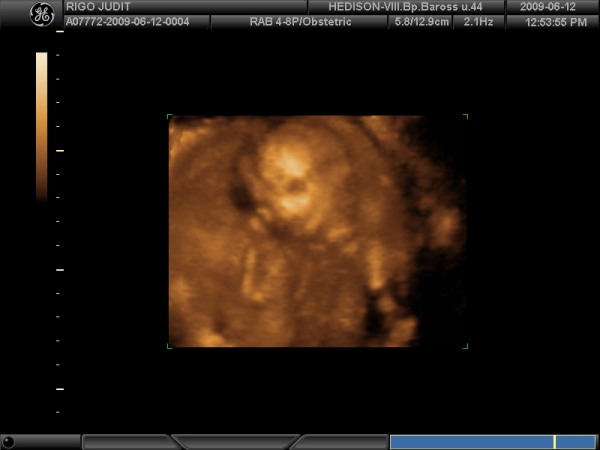

A védőnőnél ma együtt voltunk az új barinővel, kocsival vitt fel, ezért kivi is voltam a vérnyomira így hogy nem rohanásban volam és dombmászásban. Most 124/94 volt, de a pulzusom meg valamiért 122. Hát már nem tudom mi a fene van. Remélem nem kapok majd gyogyit, és csak a meleg miatt van.

A holnapi dokit már baromira várom.

Lehet hogy ezért alszom mostanában olyan rosszul, mert türelmetlen vagyok hogy rég láttam őkelmét, és szeretném már tudni hogy jól van minden oké van odabent.